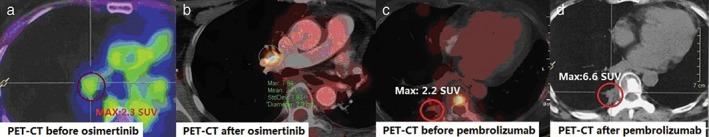

The most common EGFR mutations in non-small cell lung cancer are exon 19 deletions and exon 21 point mutations, which are both sensitive to EGFR-tyrosine kinase inhibitors. However, rare EGFR mutations do exist and how these mutations respond to tyrosine kinase inhibitors is not well understood. A Chinese woman diagnosed with stage IV lung adenocarcinoma harbored a rare EGFR L747P (2239-2240 TT > CC) mutation, and treatment with gefitinib and osimertinib failed to achieve the desired effect. Herein, possible correlations between gene analysis and the outcomes of subsequent treatment are discussed.

非小细胞肺癌中最常见的 EGFR 突变是外显子 19 缺失和外显子 21 点突变,这两者均对 EGFR-酪氨酸激酶抑制剂敏感。然而,确实存在罕见的 EGFR 突变,并且这些突变对酪氨酸激酶抑制剂的反应尚不清楚。一名被诊断为 IV 期肺腺癌的中国女性携带有罕见的 EGFR L747P(2239-2240 TT > CC)突变,吉非替尼和奥希替尼治疗未能达到预期效果。在此,讨论了基因分析与后续治疗结果之间可能存在的相关性。